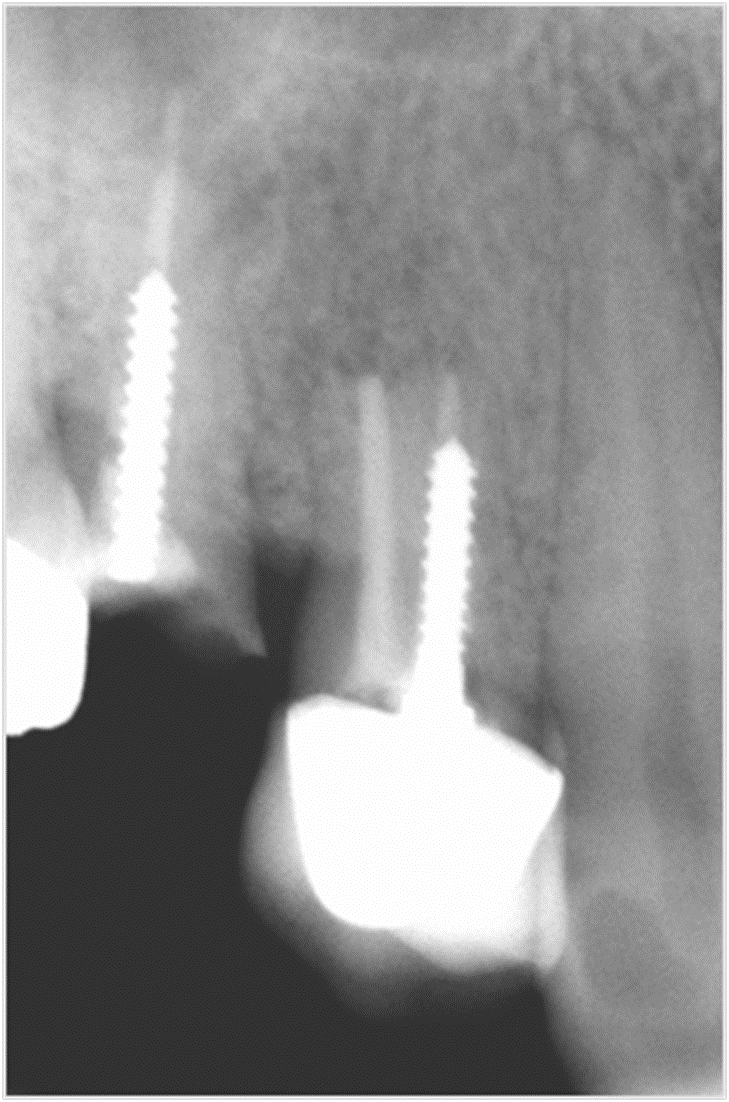

Пациентка обратилась с кариесом корня 14 зуба и 15 зуба с разрушением коронковой части зуба, ранее леченного с установкой анкерного штифта.

Имплантация 14, 15 зуба с циркониевой коронкой на импланте: